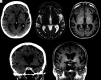

FIG 6.

Coronal T1-weighted MR imaging (A), axial T1-weighted MR imaging (B), and axial T2-weighted MR imaging (C) in a right-handed individual with impaired single-word comprehension demonstrate marked asymmetric atrophy of the anterior left temporal lobe (white arrows, A–C), suspicious for svPPA.